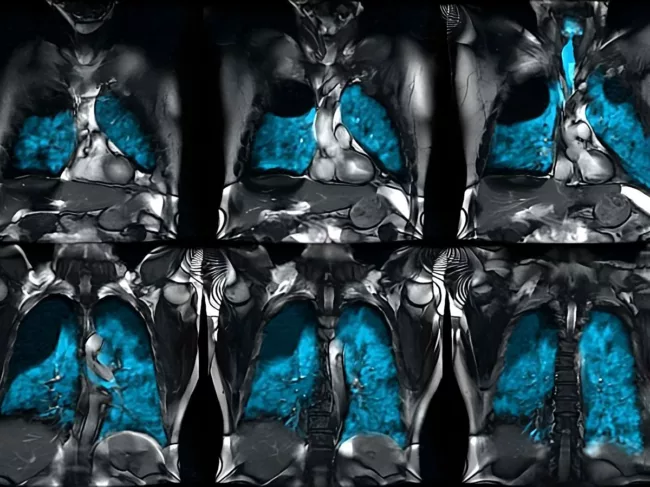

Xenoview in lungs in MRI

Polarean Imaging wins FDA nod for hyperpolarized MRI contrast agent

The U.S. FDA has approved Polarean Imaging plc’s drug-device combination product, Xenoview, for use with magnetic resonance imaging (MRI) in evaluating lung ventilation in adults and children aged 12 and older. The hyperpolarized contrast agent, which is prepared from the Xenon Xe 129 gas blend, is expected to be commercially available in the U.S. starting next month. Read More